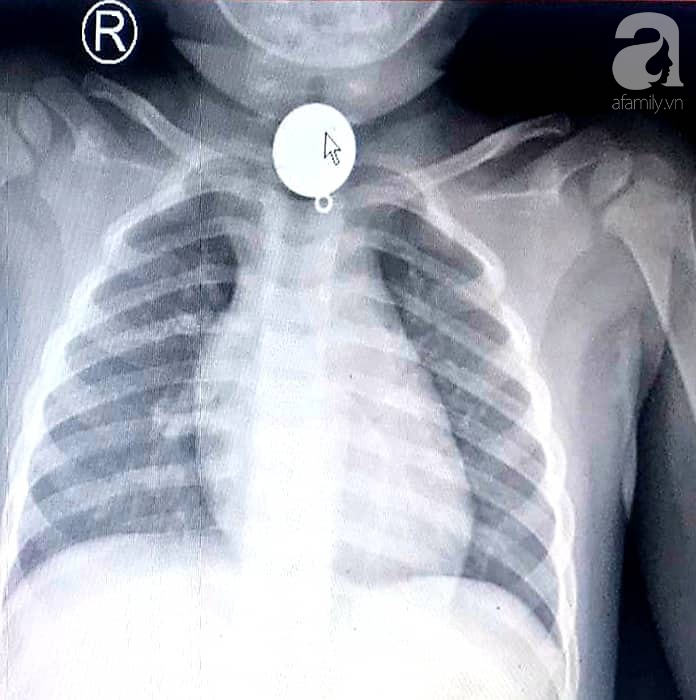

Kết quả chụp X-quang ngực phát hiện dị vật, bé được chuyển ngay đến Bệnh viện Nhi đồng Thành phố (TP.HCM).

Nhận định dị vật mắc trong cổ bé rất to, hình tròn nằm chiếm hết lòng đầu trên thực quản, các bác sĩ chẩn đoán khả năng dị vật gây trầy, rách thực quản hay hóc ngược vào đường thở rất cao nếu xử trí không khéo.

Ảnh chụp X-quang thấy rõ dị vật hình tròn nằm chiếm hết lòng đầu trên thực quản.